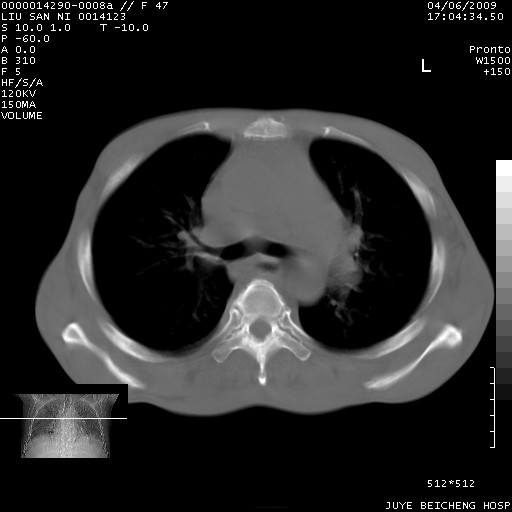

以下是引用前行在2009-4-7 10:31:00的发言:[br]肝脾肿大;双肾增大,双肾盂少量积水可能,肾膜膜增厚,肾周间隙增宽,并见桥间隔,提示结缔组系统疾病、系统性红瘢狼疮肾可能性大。继发右侧胸腔、心包、腹腔积液。